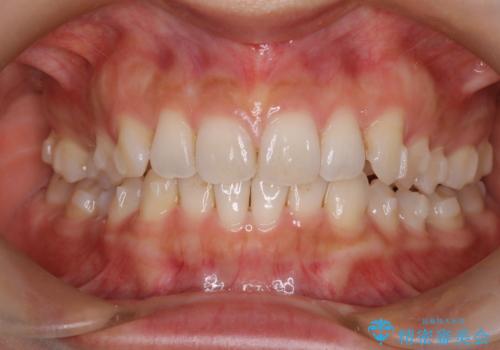

【インビザライン】前歯のねじれを治したい

- 前歯のガタガタを主訴に来院されました。

叢生の量は軽度でしたが臼歯の遠心移動を行い、インビザラインにて治療をしました。

叢生の改善に必要なスペースは遠心移動やIPRで作ることが可能です。今回は遠心移動をメインにスペースを作って叢生の改善を行いました。